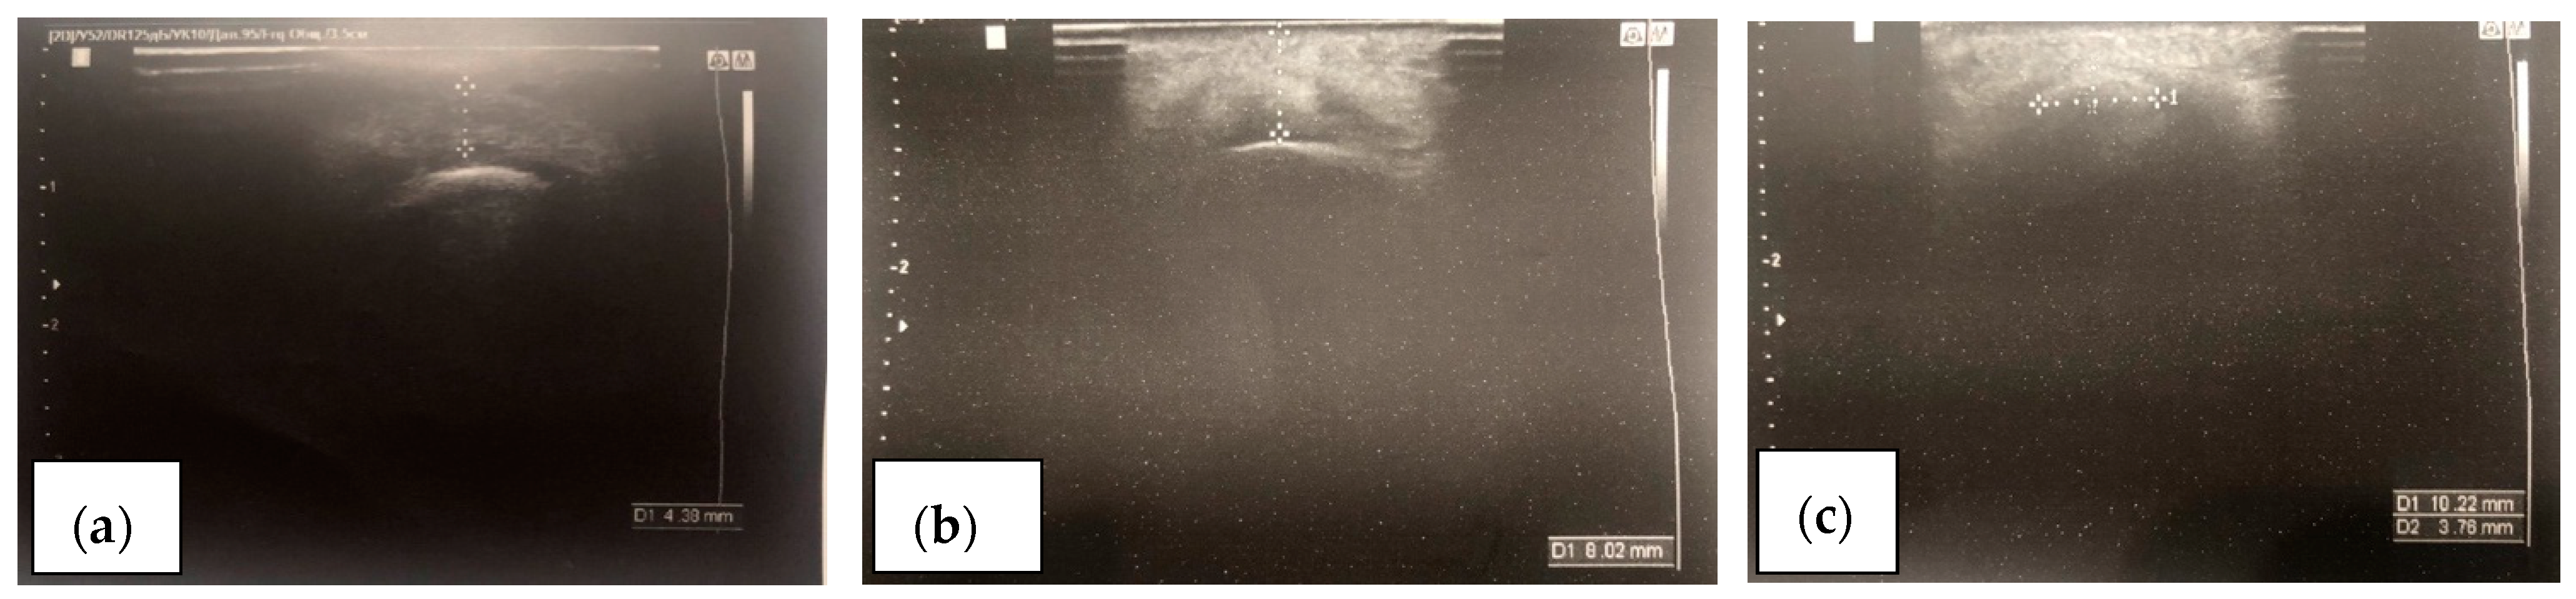

The maximum increase in chin projection was observed in the early postoperative period. This phenomenon was associated with the development of swelling and the initial autograft integration phase. However, in the later stages of the rehabilitation period, the fat autograft underwent minor resorption and the formation of fibrous connective tissue in the surrounding structures, contributing to the partial volume loss. Ultrasound imaging of the chin’s soft tissues showed clear visualization of the fat autograft boundaries (Figure 5). Ultrasound examination was also used to evaluate the volume of soft tissues from the bony structure of the chin area to the skin. Table 2 presents the average values of the soft tissue augmentation at the pogonion point. The potential error caused by the pressure of the ultrasound probe on the soft tissues of the chin area at the pogonion point was eliminated. In Doppler scanning mode, pronounced vascular blood supply is challenging to detect; however, histological analysis and the identification of arterioles and capillary structures confirm the presence of blood supply (Figure 6).

Figure 5. Ultrasound examination of the subplatysmal fat autograft distribution in the chin area: (a) preoperative image; (b) assessment of the height of the subplatysmal autograft volume at 12 months in the chin projection; and (c) assessment of the width of the subplatysmal autograft volume at 12 months.